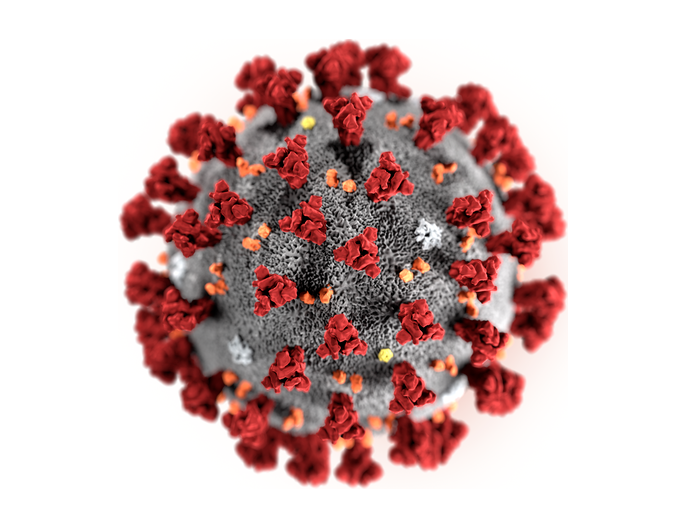

Bei schweren Krankheitsverläufen von COVID-19 kommt es, anders als bislang allgemein angenommen, nicht allein zu einer starken Immunreaktion –…

Würzburger Forschergruppe druckt das erste biologisch korrekte 3D-Modell des SARS-CoV-2 Virus. Eine Anleitung für den 3D-Druck und die Bemalung des…